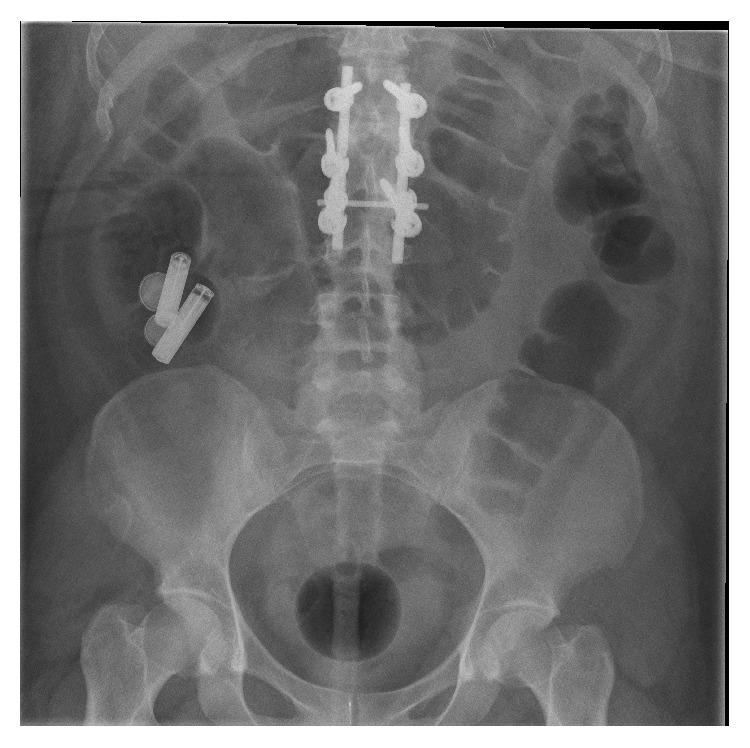

Ingestion of foreign bodies and particularly of button or/and cylindrical batteries is frequent in children and adults with underlying psychiatric diseases. We present a case of a 30-year-old woman with unstable borderline disorder, where overall 4 button and 2 cylindrical batteries were endoscopically removed from her digestive system. During the last session of colonoscopy a peculiar incident was observed, as a cylindrical battery of 15 mm diameter and 43 mm length moved retrograde through ileocecal valve into the small bowel. The foreign body removal from terminal ileum was effective and safe using an endoscopic loop. This report suggests that endoscopic insertion in terminal ileum should be attempted in every colonoscopy session conducted under the indication of foreign body removal, as the possibility of retrograde movement of even large foreign bodies in the colon and through ileocecal valve is given.